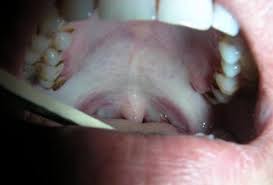

Buccal SCC commonly presents as a slow-growing mass on the buccal mucosa.

- Synchronous SCC of the buccal mucosa

- Papillary SCC of the buccal mucosa

Small lesions tend to be asymptomatic and are often noted incidentally on dental examination.

Pain commonly occurs as the lesion enlarges and ulceration develops.